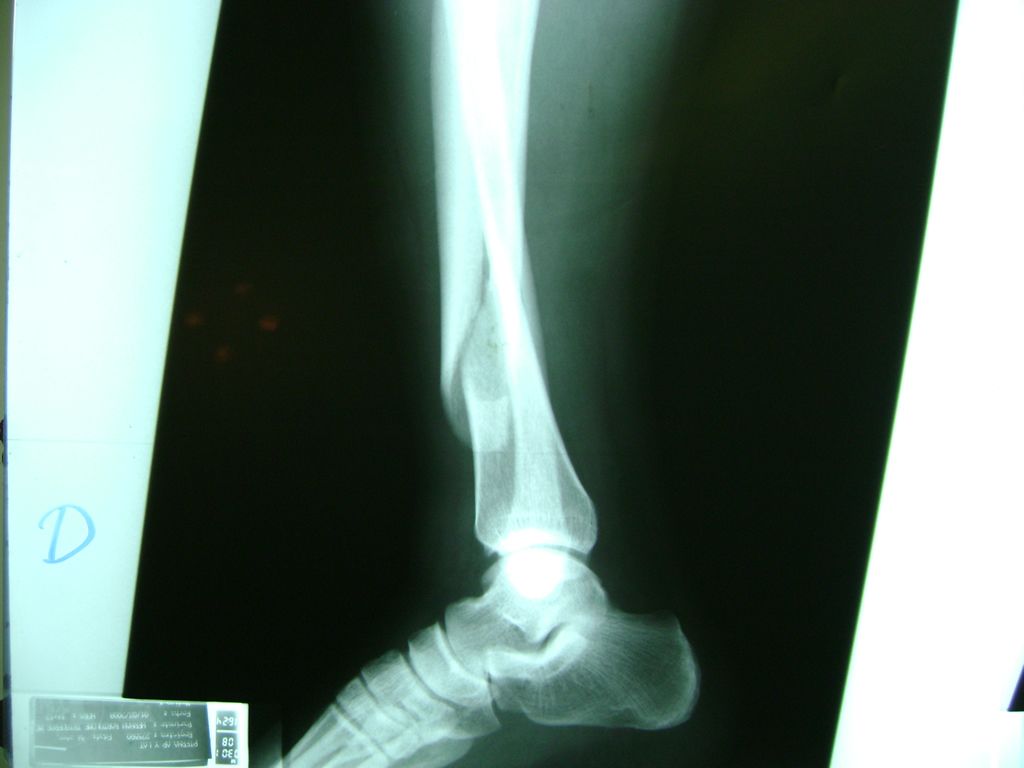

Cirugías de Tobillos

Aunque cada uno de estos huesos puede fracturarse por separado, normalmente la rotura es una lesión que se produce de forma conjunta

La mayor parte de las roturas implican a la parte proximal del hueso (parte del hueso próximo a la rodilla) o a la parte distal (parte del hueso cerca del tobillo).

Debido a la fina cobertura de piel que recubre la tibia y el peroné, las fracturas generalmente son abiertas, es decir, el hueso roto rasga la piel, atravesándola. Las fracturas de tibia y peroné generalmente se producen por un fuerte impacto o torsión.